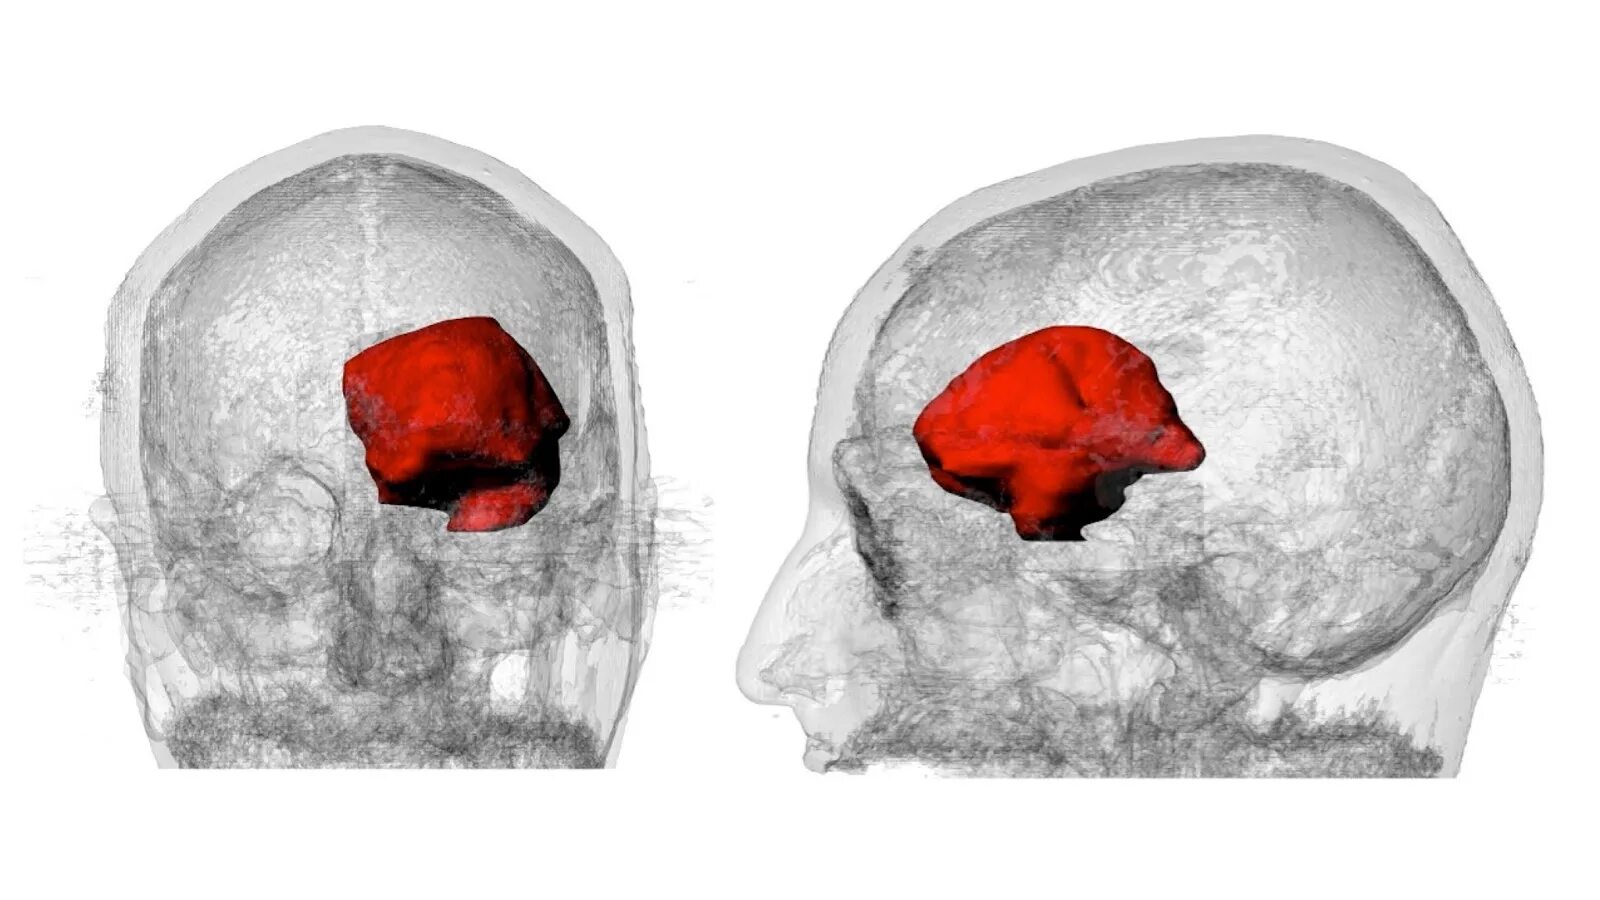

Как умирают от рака головного мозга